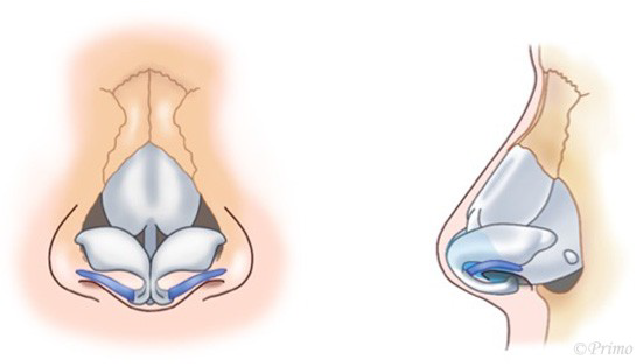

青い部分が移植した軟骨です。この軟骨の固定により、鼻の高さ、細さ、向きが大きく調節できます。

Laterl crural graft

細くなりすぎた鼻先を自然に整えたい場合などに用います。

Rim graft

ピンチノーズの修正に用いることがあります。鼻孔縁をほんの少しだけ下げる効果が期待できる場合があります。

Columellar graft

鼻柱をさらにしっかりと下ろしたい場合に用います。鼻柱の形にこだわりがある場合にも、希望の形に近くなるよう形成し用います。鼻の下が短くなる効果も期待できます。

Shield graft

鼻柱上部から鼻先を斜め下方向に出す効果があります。鼻柱基部から鼻先が直線的にならず、横から見ていわゆる四角形の鼻先を形成するために用いることもあります。

Onlay cap graft

鼻先にもう少し高さが欲しい場合に用います。鼻先をほっそりと見せる効果もあります。希望の鼻先の向きを叶えるための微調整に用いることもあります。